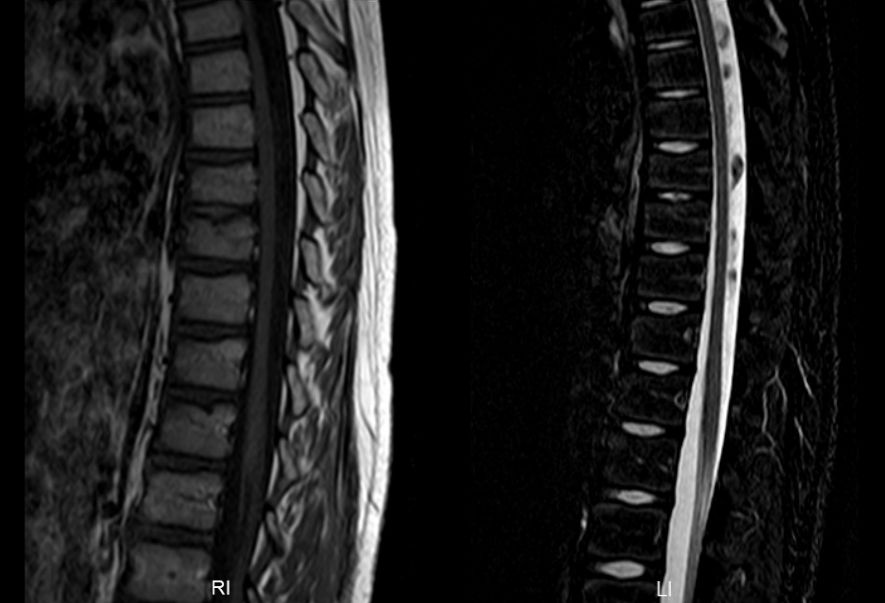

综合以上检查,诊断考虑“病毒性脑脊髓炎”。予“阿昔洛韦”抗病毒、“金璐捷”营养神经、“甲强龙”激素冲击等对症治疗15天,好转后出院。出院后继续口服“强的松”治疗1年余。出院后平时可下地行走,但未能坚持长时间,爬楼梯吃力,可短程小跑,剧烈运动或行走时间长后有腰背部疼痛、四肢酸痛,休息后可好转,感冒后症状加重,行走困难,站立不稳,伴腰背疼痛及排尿困难,有时大便失禁。感冒好转后症状可缓解,恢复至平时状态。现双下肢可行走,无腰背部疼痛、四肢酸痛,来院复查磁共振见脊髓粗细正常,未见明显异常信号(图2),为进一步诊治,门诊拟“病毒性脑脊髓炎”再次收住入院。

图2. 治疗1年后复查头颅及全脊髓磁共振:左侧小脑半球与前片比较异常信号基本消失。全脊髓粗细正常,未见明显异常信号。